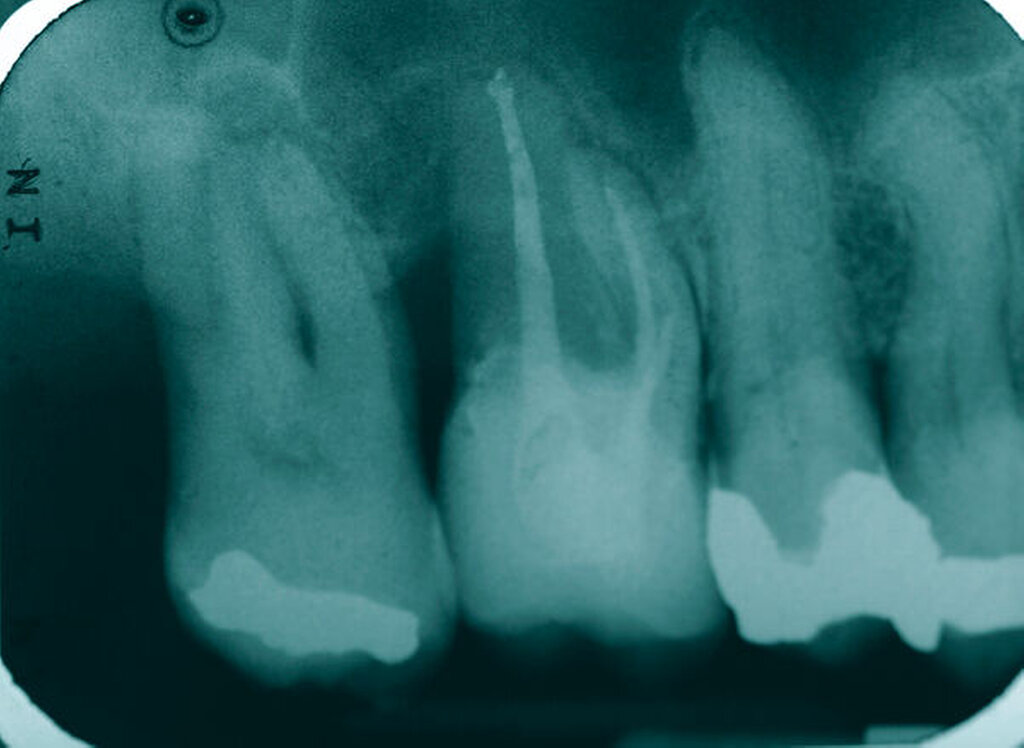

Tiefer kariöser Defekt (Fall Nr. 10)

Eine 53-jährige Patientin stellte sich 2015 mit plötzlich aufgetretenen, starken Beschwerden an Zahn 16 und der Bitte um Abklärung vor. Es erfolgte die klinische und röntgenologische Befundung des Zahnes, der neben einer apikalen Parodontitis auch eine große, fast bis in die Furkation reichende Kronenrandkaries an der mesiobukkalen Wurzel aufwies. Um diesen vorhersagbar versorgen zu können, wurde der Patientin die endodontische Behandlung mit Amputation der mesiobukkalen Wurzel und anschließender Versorgung mittels Vollkrone als Alternative zur Extraktion aufgezeigt. Sie entschied sich für den Zahnerhalt.

So folgte nach der Wurzelfüllung die Amputation der mesiobukkalen Wurzel. Der Zahn wurde nach der Amputation auf Wunsch der Patientin zunächst mit einem Langzeitprovisorium versorgt, das im Verlauf gegen eine definitive Versorgung ausgewechselt wurde. Die Patientin ist seitdem an 16 beschwerdefrei, der Zahn ist stabil und hat eine gute Langzeitprognose.